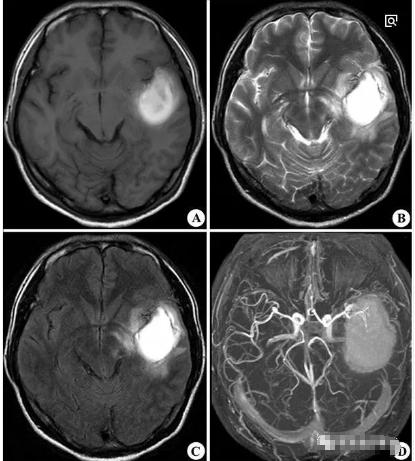

三、脑叶出血:

也称为皮质下白质出血,可发生于任何脑叶。除表现头痛、呕吐外,不同脑叶的出血,临床表现亦有不同。

如:额叶出血可出现精神症状,如烦躁不安、疑虑,对侧偏瘫、运动性失语等;顶叶出血则出现对侧感觉障碍;颞叶出血可出现感觉性失语、精神症状等;枕叶出血则以偏盲最为常见。脑叶出血一般症状均略轻些,预后相对较好。

左侧颞叶高密度影,呈短T1长T2信号,周围可见长T1长T2水肿信号。